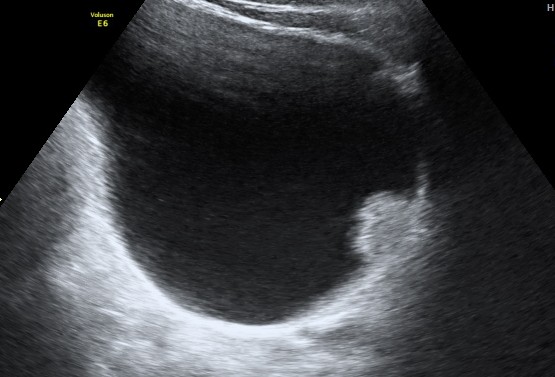

the last case was vesical calculi ; this one was a urinary bladder carcinoma .

47 year old man presented with complaints of painless hematuria ; he had a similar self limiting episode 3 months ago , which he ignored.His ultrasound pictures are given below

the next is a post void picture showing the mass